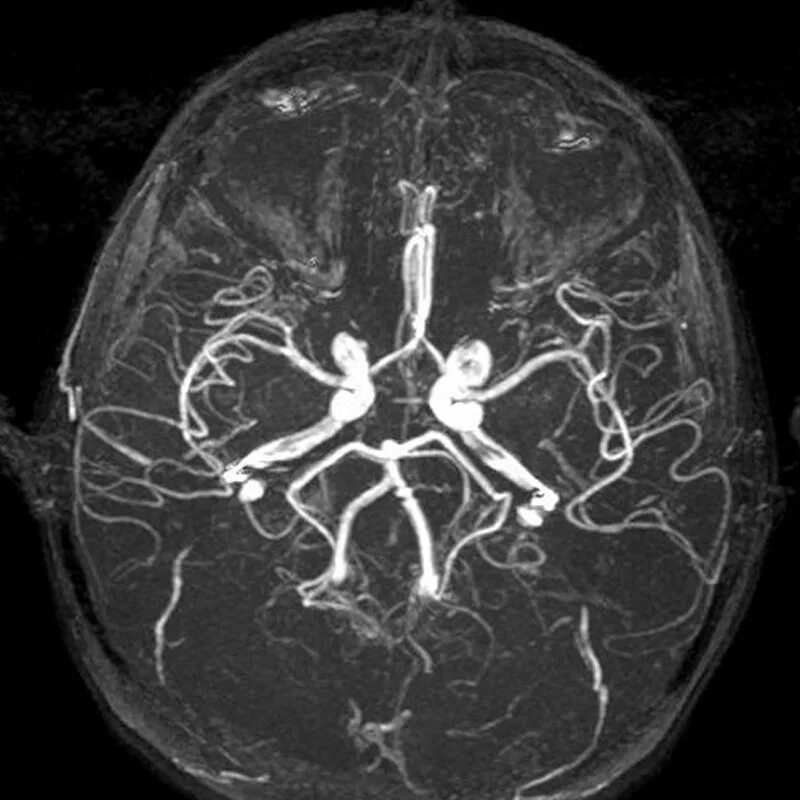

Что покажет мрт головного мозга с контрастом